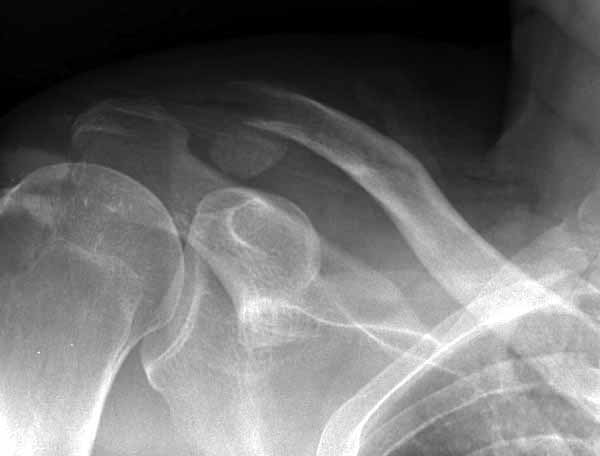

Из заданного вопроса в этом посте я понял, что разговор идет по поводу “методики применения ключичной пластины с крючком при акромиальных переломах”, т.е не ведется разговор “по поводу лечения косых переломов ключицы”.

По поводу пластины с крючком, Ваше заключение "не вижу препятствий для фиксации акромиального косого перелома ключицы для МОС использовать пластинку с крючком" вызывает сомнение.

Предназначенную для лечения повреждений связочного аппарата акромиально-ключичного сочленения пластину можно применить не при всех переломах акромиального конца ключицы. Потому что имплант рассчитан на интактную ключицу и не для переломов ключицы. Пластина короткая, не покрывает медиальный диафизарный фрагмент ключицы и за счет тракции стерноклеидомастоидеус такая фиксация прорвется через несколько дней.

Имя     : 1 Clavicle AC injury.jpg

Тип     : image/jpg

Размер  : 25274 байтов

Описание: отсутствует

Url     : http://weborto.net:8080/pipermail/ortho/attachments/20110623/6adf8600/attachment-0006.jpg